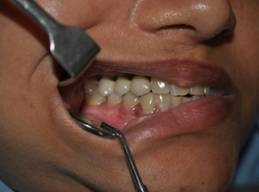

INTRA ORAL IMAGES

OCCLUSION REHABILITATION

BALANCED OCCLUSION REHABILITATION